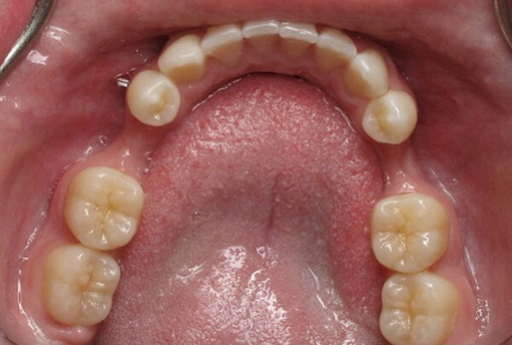

Tại Nha khoa Olympia, các cô chú/anh chị mất răng đến thăm khám kiểm tra tình trạng răng đã làm cầu răng sứ bị hỏng: ...[Xem thêm]